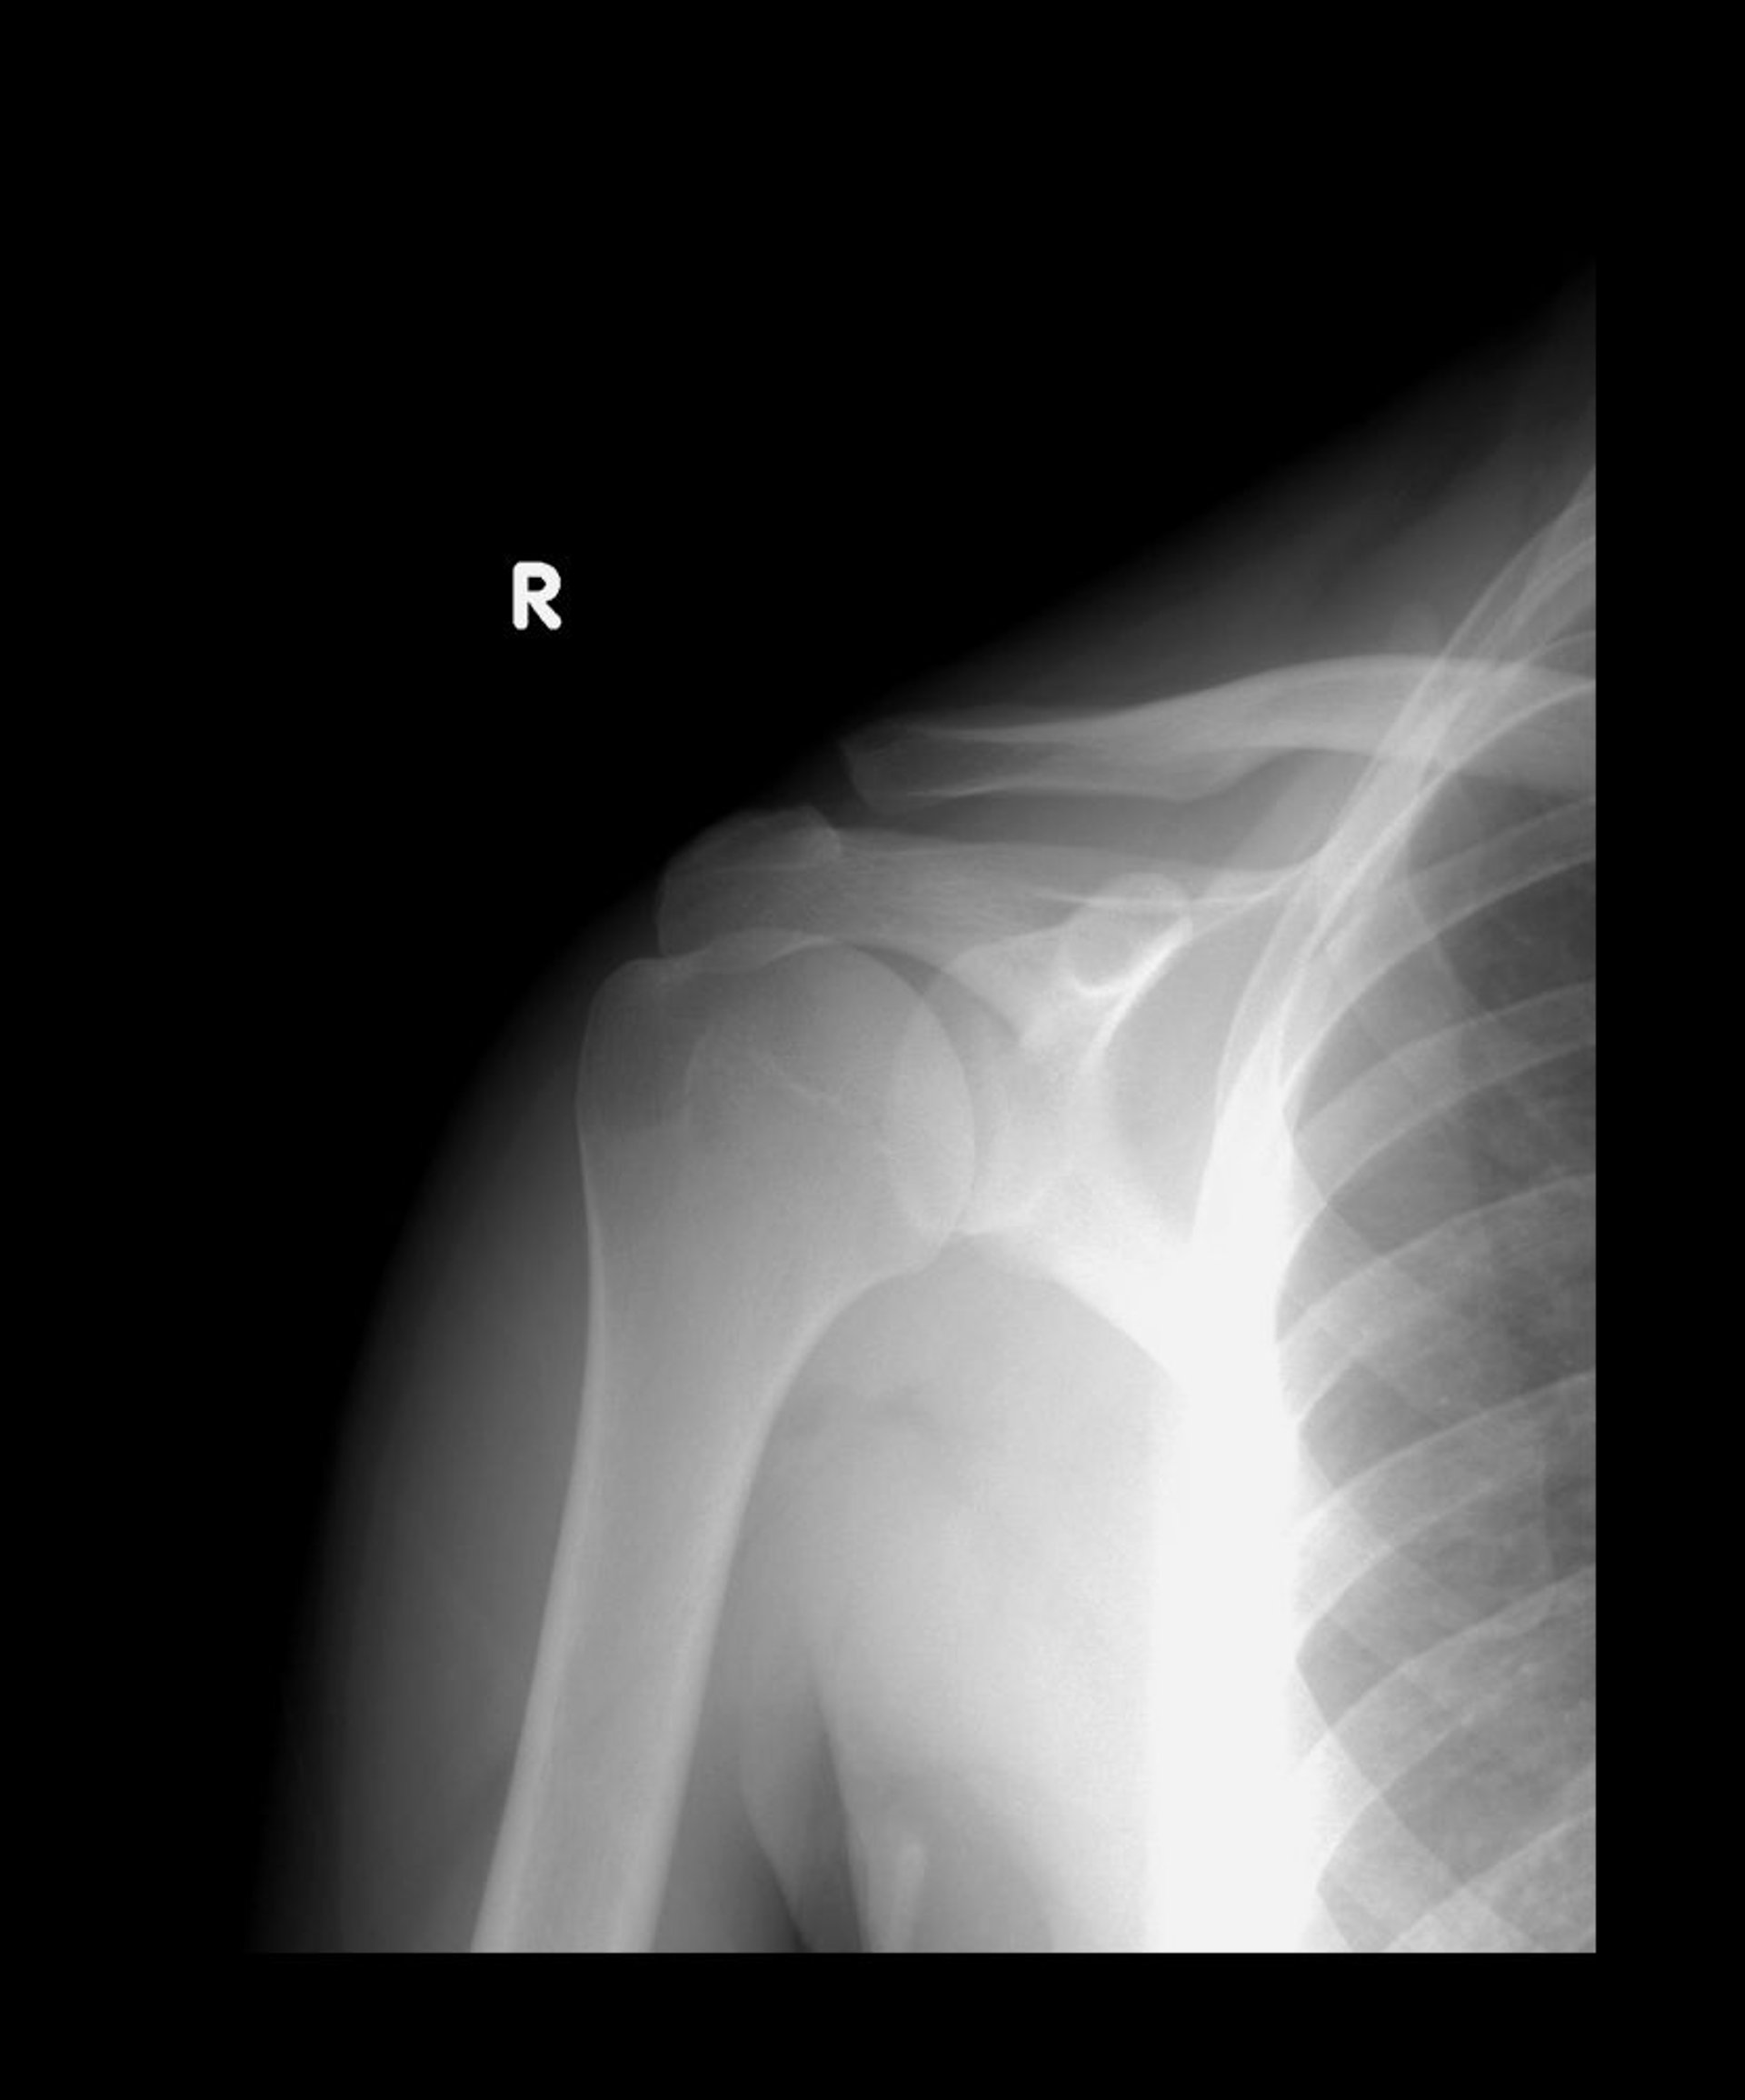

Acromioclavicular Joint Sprain

Normally, the lower ends of the acromion and clavicle align. In this radiograph, the clavicle is displaced upward but the 2 bones still overlap, suggesting a type II subluxation.

LIVING ART ENTERPRISES, LLC/SCIENCE PHOTO LIBRARY